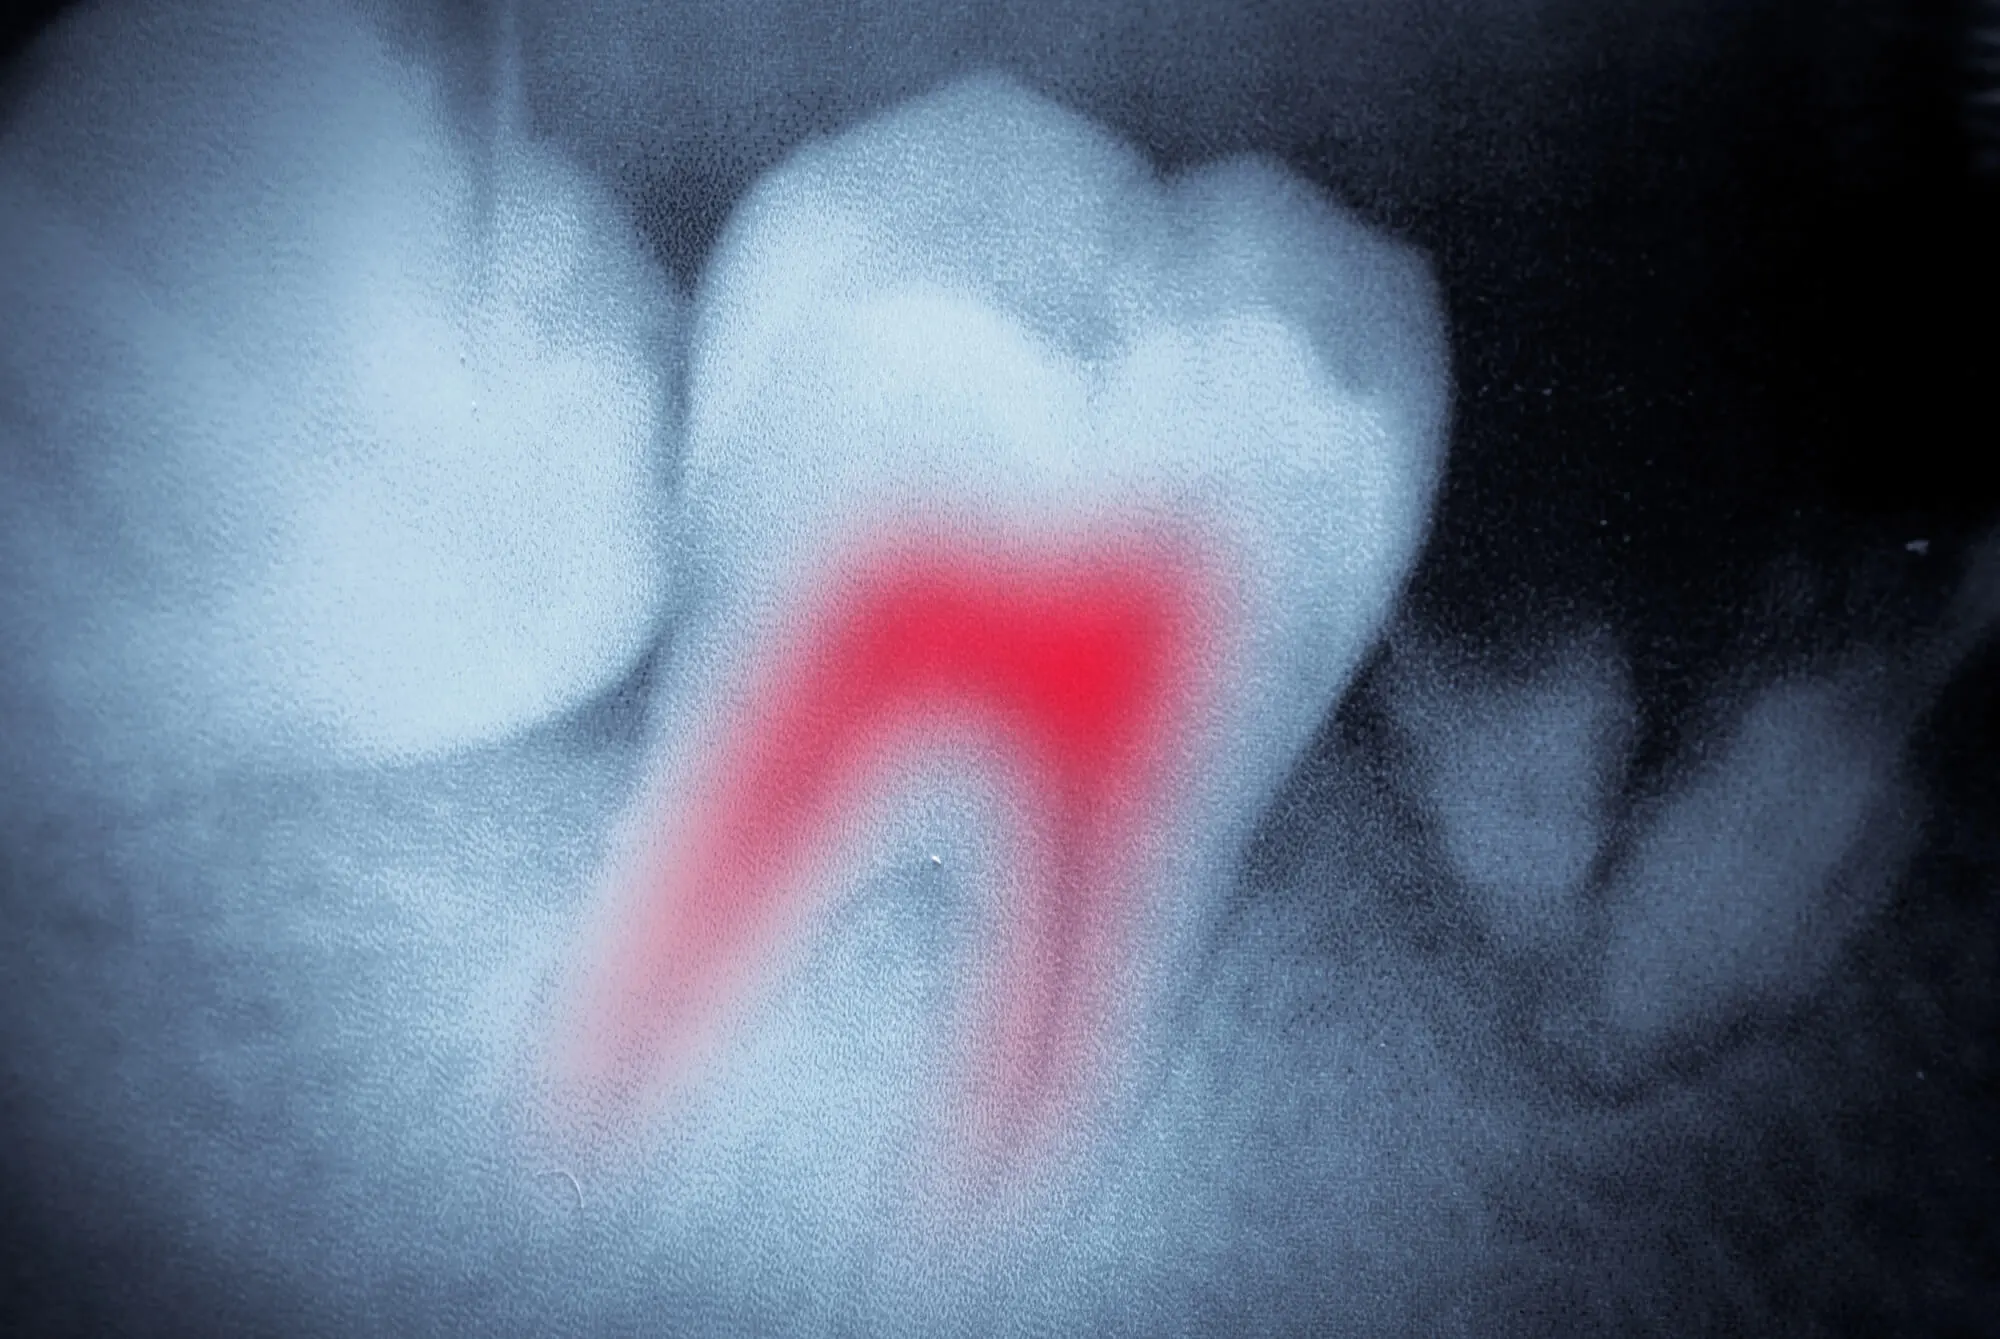

Endodontics in Davie, FL, focuses on the inside of the tooth—the pulp, where nerves and blood vessels reside. When infection from a cavity or inflammation reaches this inner layer, it can cause serious pain, risk losing the entire tooth, and even threaten the health of your jawbone.

Tooth pain, sensitivity to hot or cold, or swelling in the gums can be signs that the pulp inside your tooth is infected. This can result from deep decay, a cracked tooth, or a dental injury. If left untreated, it may lead to a painful infection known as an abscess or tooth loss.

Endodontic treatments like root canal therapy aim to remove this infected tissue, preventing the need for more invasive treatments, like dental extractions.